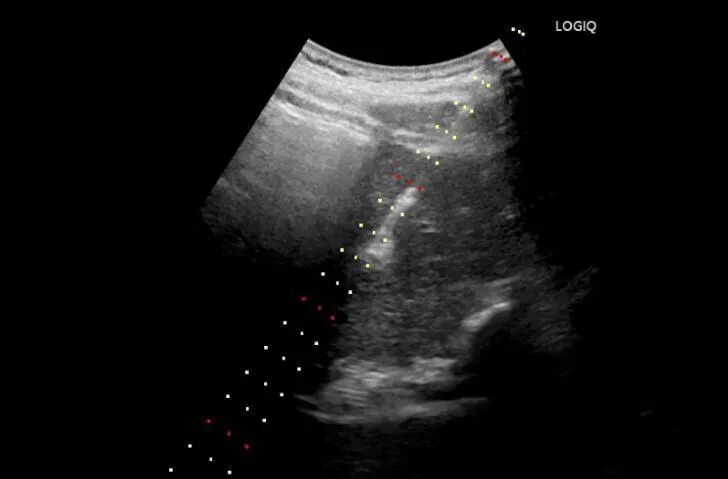

患者男性,年龄,发现肝占位一月余,于2026-03-31在超声引导下行肝占位穿刺活检。

(超声引导下可见红色区域为肝内占位灶,黄色区域为伴行动脉)(超声引导下可见红色区域为肝内占位灶,黄色区域为伴行动脉)

术后病理提示:胰腺神经内分泌癌肝转移。该技术极大减少了危险部位及出血高危患者的出血风险,尤其适用于肝、肺、肾等血供丰富组织的穿刺活检。同时减少了穿刺次数,降低患者穿刺痛苦。